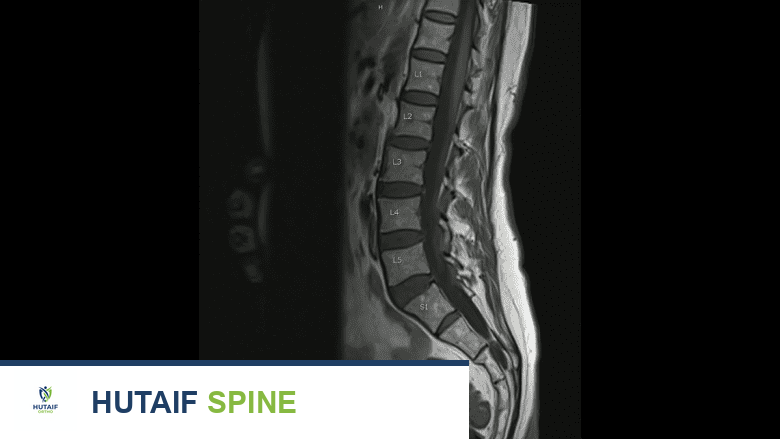

- التصوير الطبي والفحوصات المخبرية: تُستخدم تقنيات التصوير مثل الأشعة السينية (X-ray)، والتصوير بالرنين المغناطيسي (MRI)، والتصوير المقطعي المحوسب (CT) لتقييم حالة المفاصل الوجيهية، وتحديد مدى التلف أو الالتهاب، واستبعاد مشاكل أخرى مثل الانزلاق الغضروفي أو تضيق القناة الشوكية. في بعض الحالات، قد تُجرى فحوصات مخبرية إضافية.

يكشف فحص الرنين المغناطيسي عن تلف والتهاب في المفاصل الوجيهية.

في عيادة الأستاذ الدكتور محمد هطيف، يتم استشارة أطباء علاج الألم، وأخصائيي التخدير، وجراحي العمود الفقري (مثل الأستاذ الدكتور محمد هطيف نفسه) لإجراء التقييم الأولي وحقن الأعصاب الفرعية الإنسية. تضمن هذه الشمولية تقديم أفضل رعاية ممكنة للمريض.